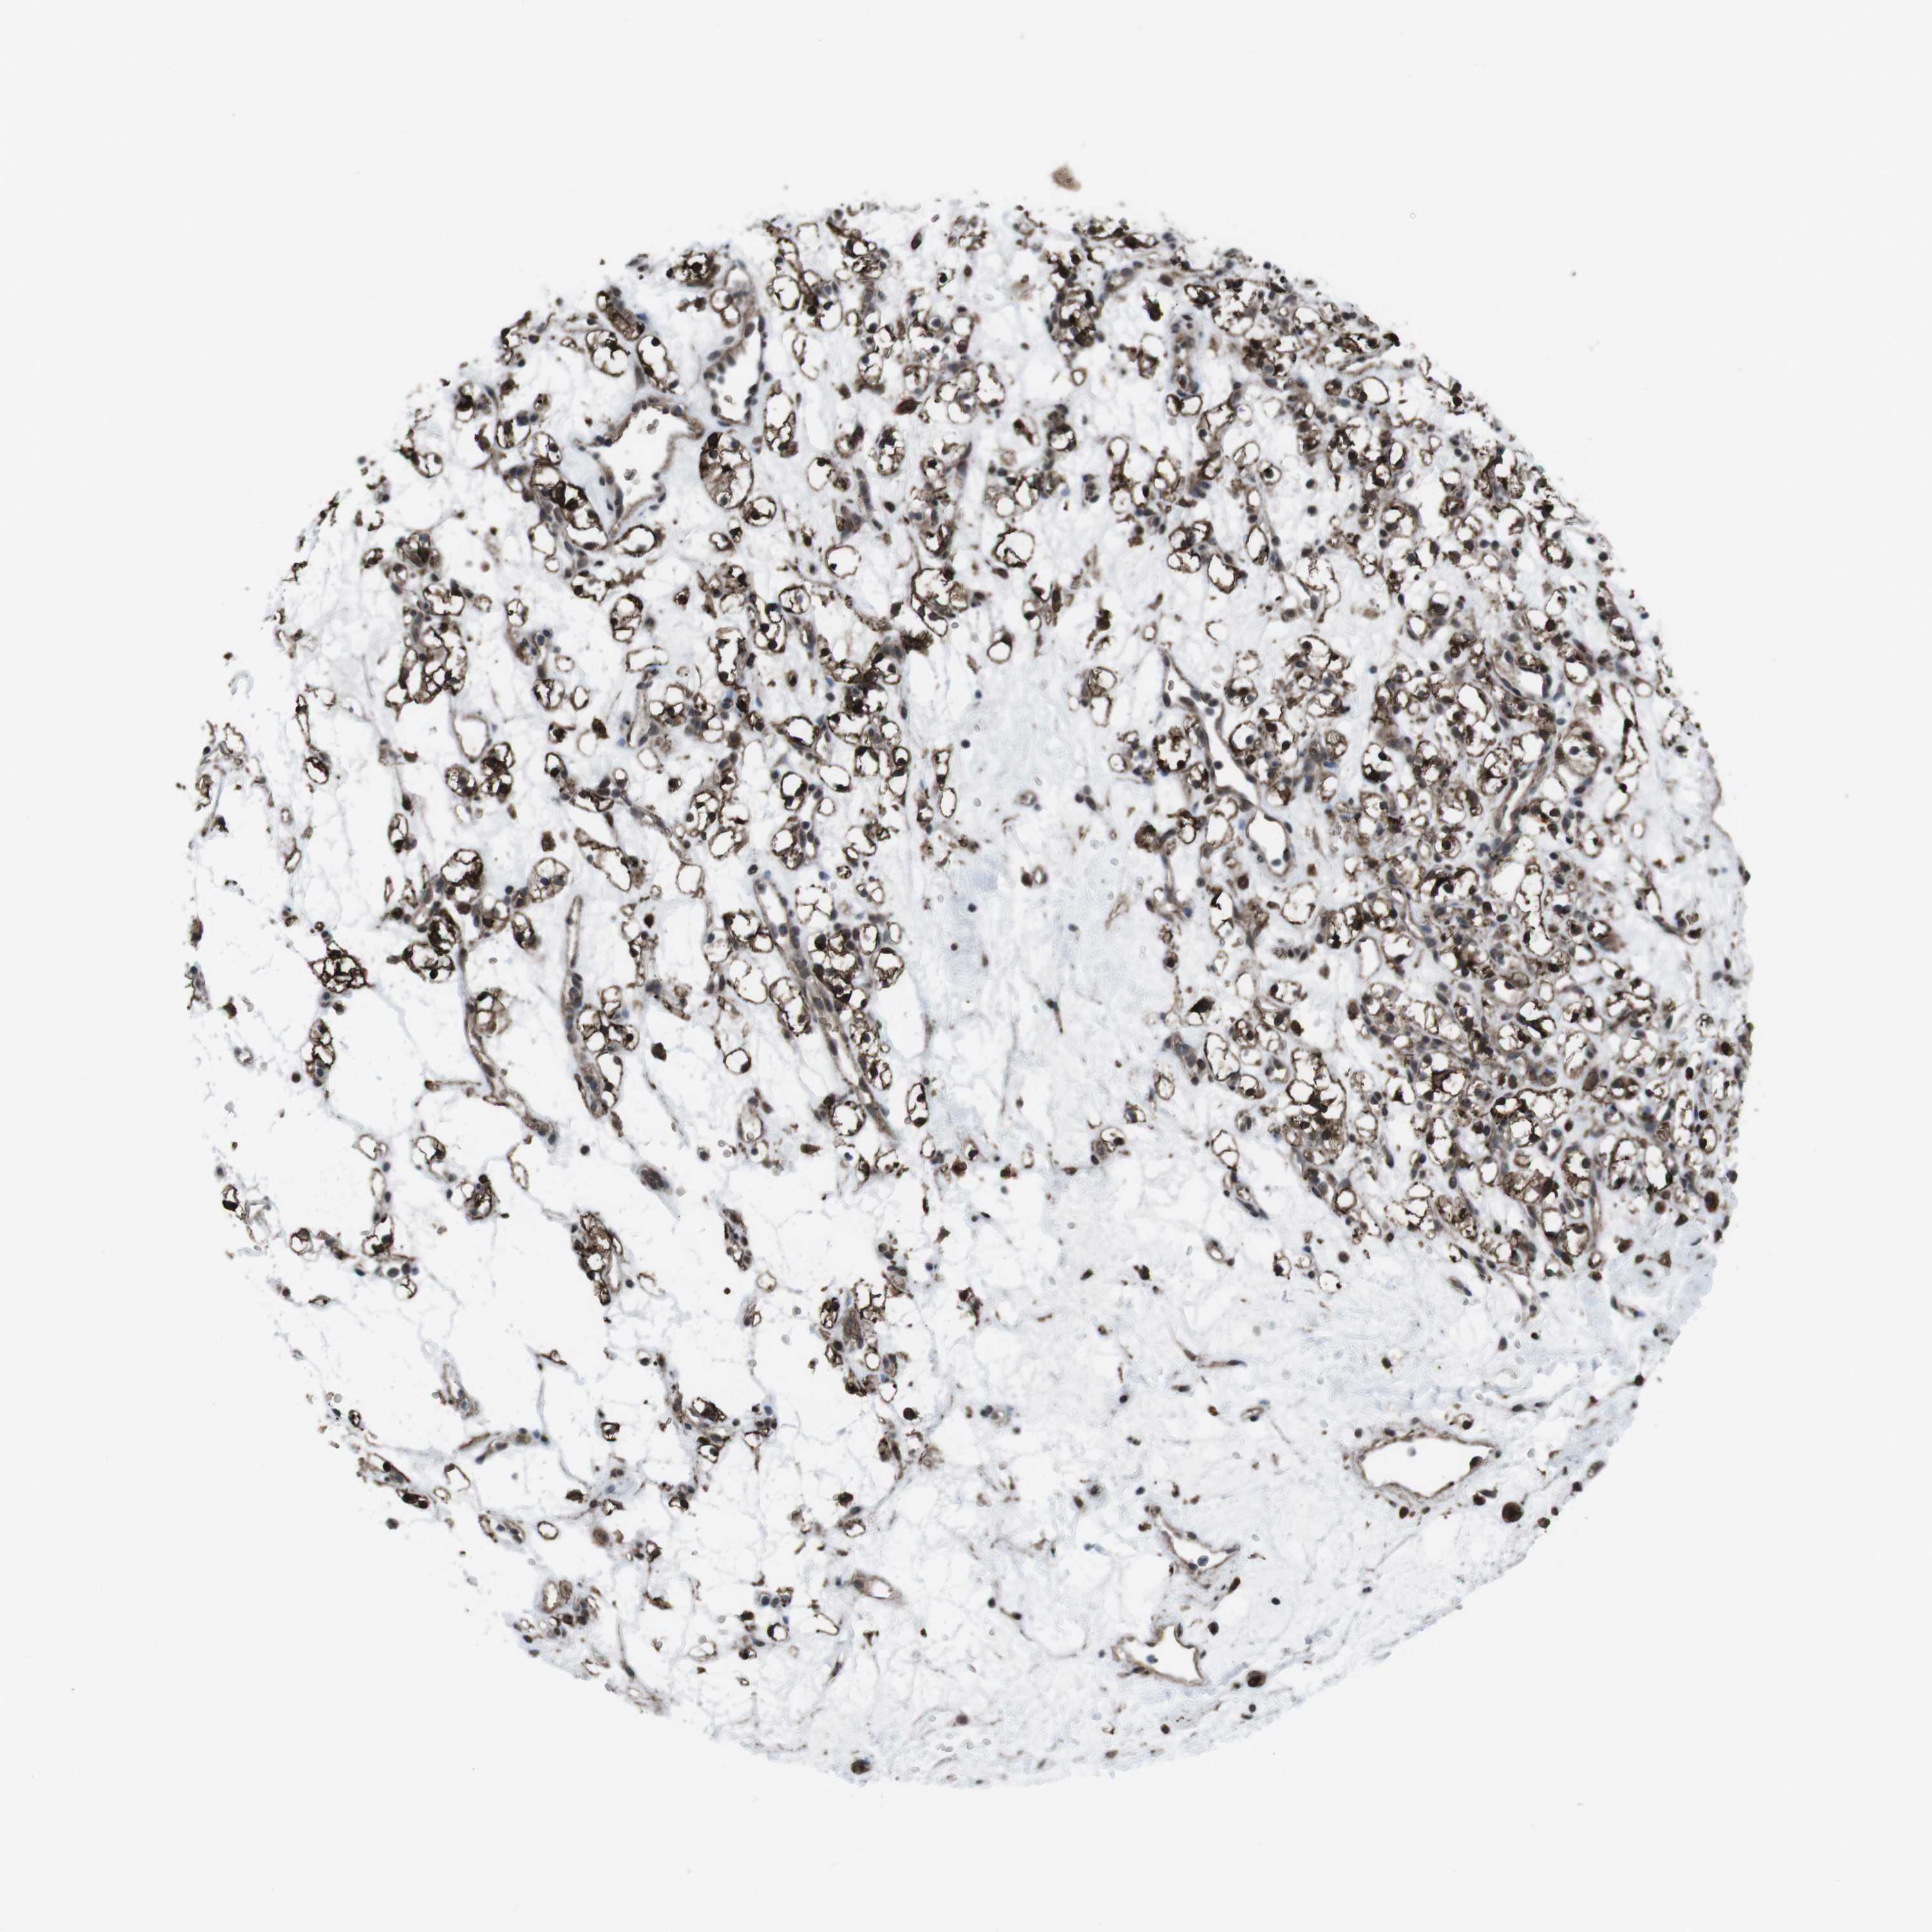

TCGA RNA samplesi

RNA-seq data is reported as average FPKM (number Fragments Per Kilobase of exon per Million reads), generated by the The Cancer Genome Atlas (TCGA) .

Normal distribution across the dataset is visualized with box plots, shown as median and 25th and 75th percentiles. Points are displayed as outliers if they are above or below 1.5 times the interquartile range. FPKM values of the individual samples are presented next to the box plot.

Average pTPM 0.2

Number of samples 521